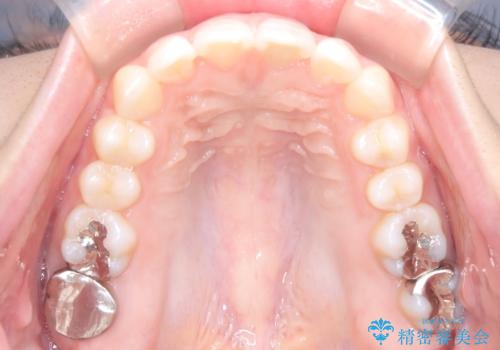

- 前歯が出ていることを主訴に来院された患者様です。

抜歯を希望されなかっため、臼歯部の遠心移動やIPRを行い配列を行っています。

抜歯をしていない矯正となるため、口元に大きな変化は認められません。